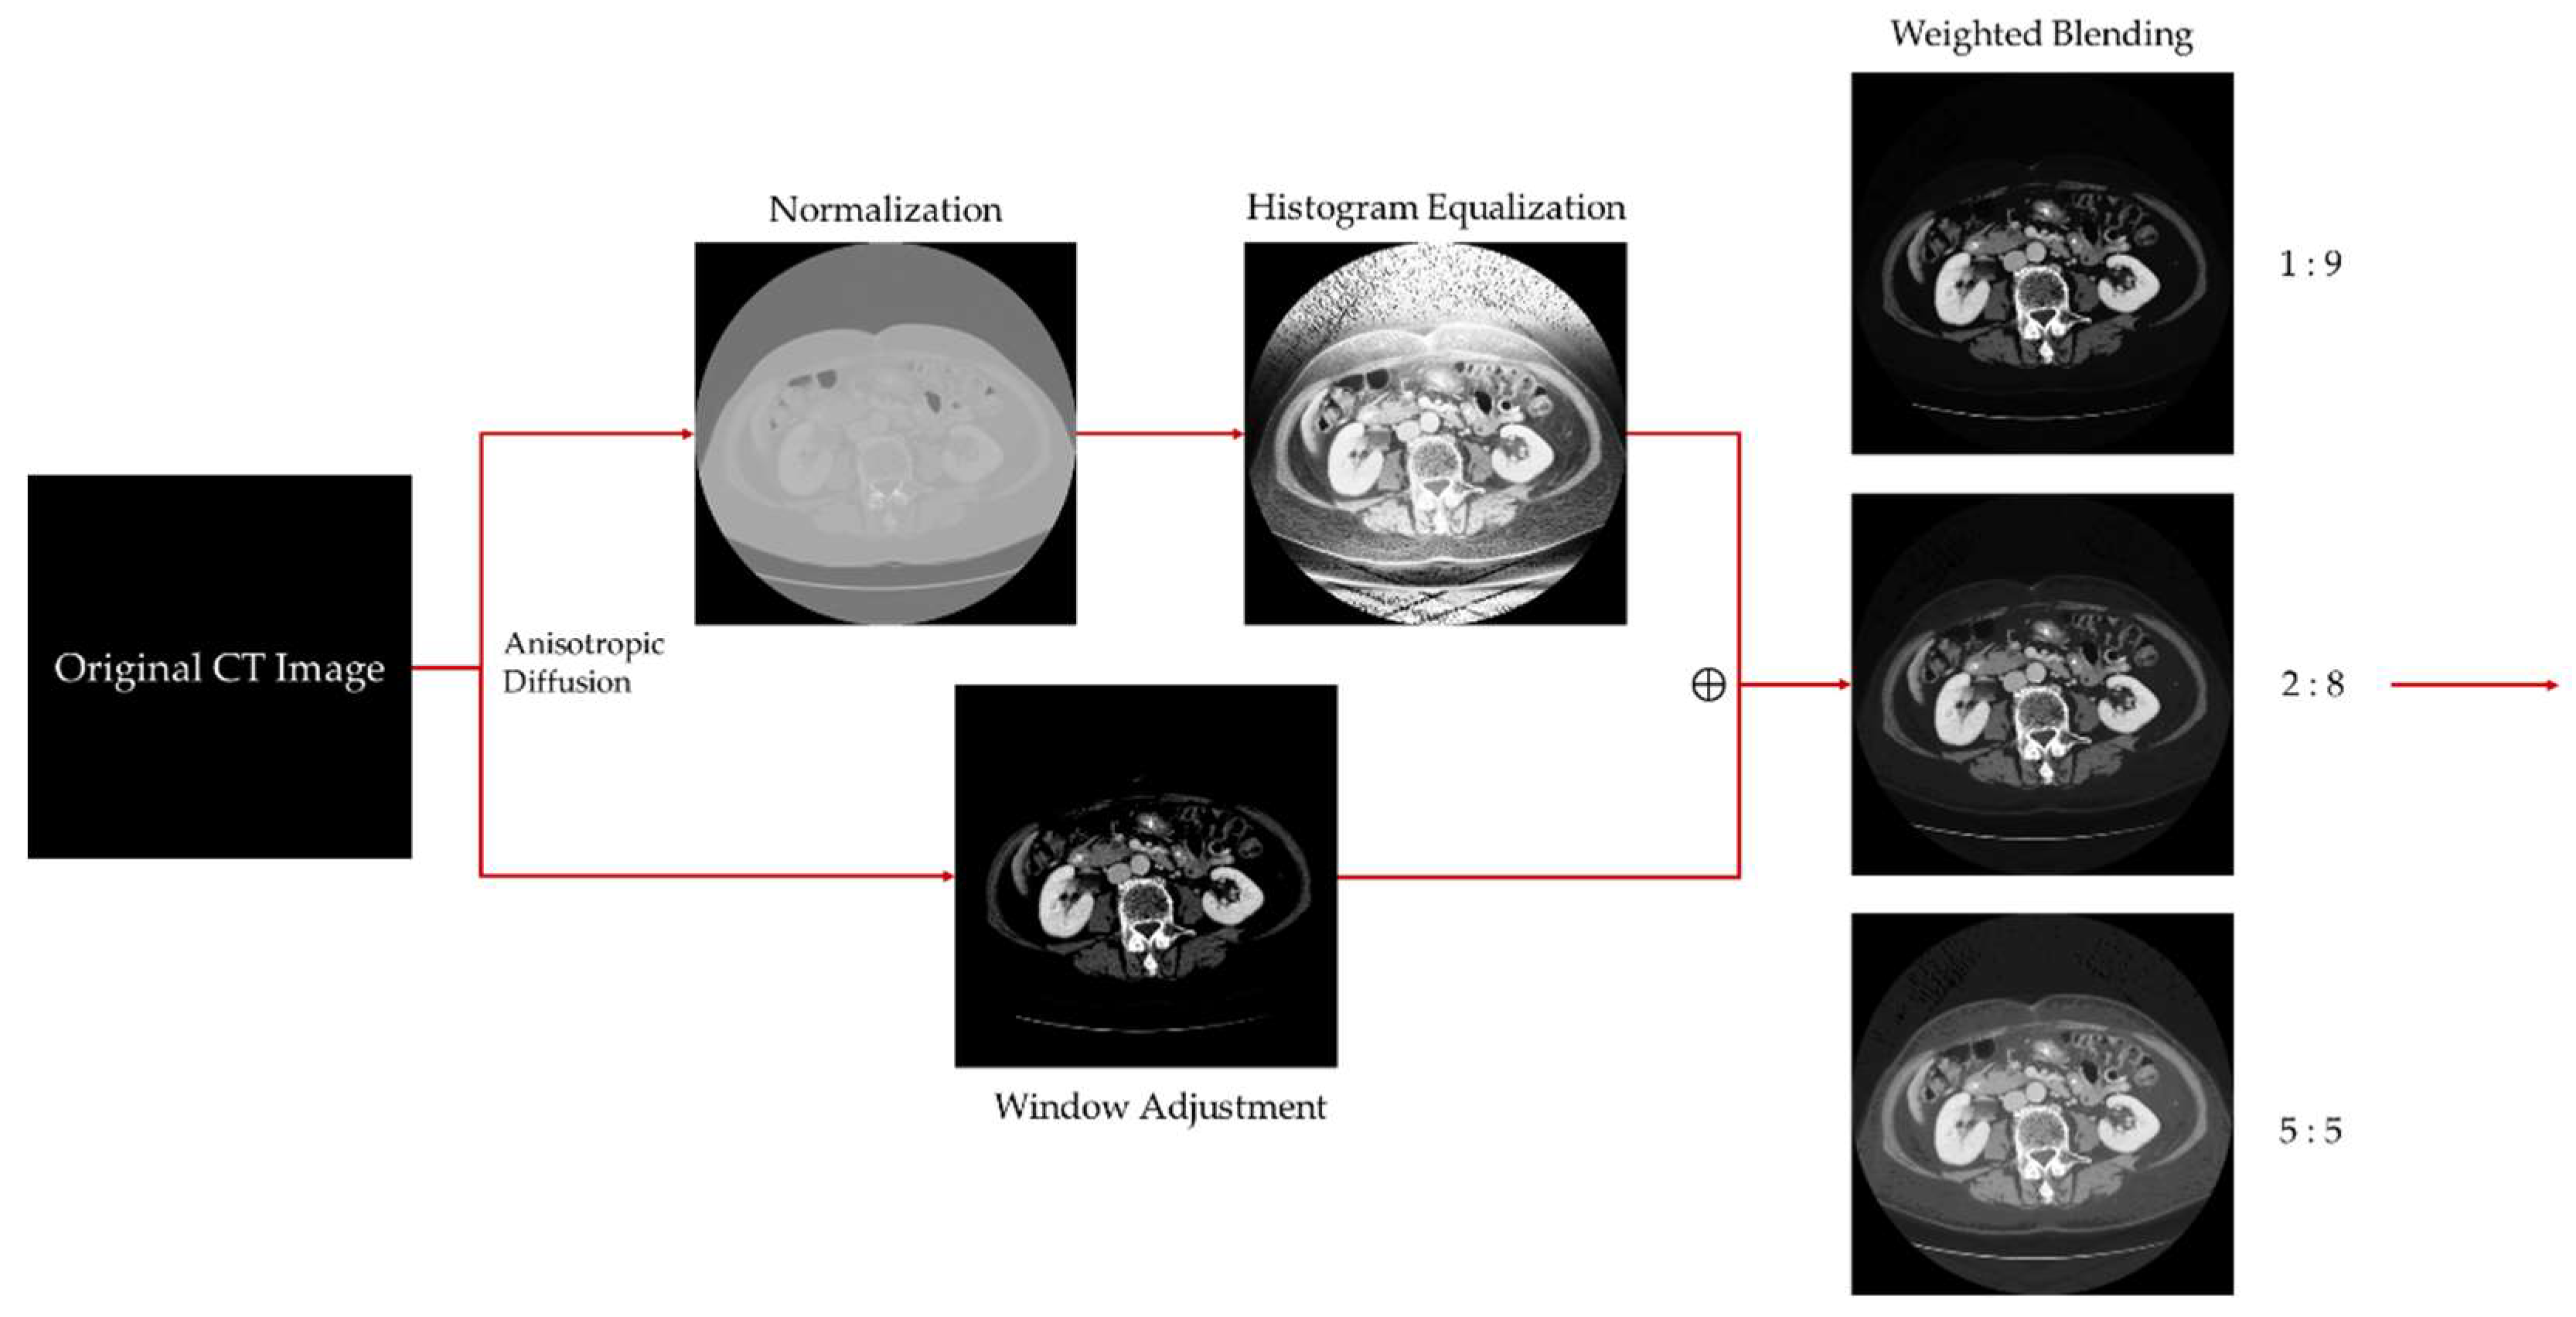

- Digital image enhancement strategies for medical image features: Medical images often contain a high level of noise and details hidden in low-intensity regions. To address this, anisotropic diffusion filters are used for denoising, and histogram equalization is employed to enhance the texture and details of medical images globally. Additionally, the fusion of window level and window width adjustment techniques specific to medical images is applied to target the regions of interest within the image. These strategies aim to achieve global enhancement of medical images while highlighting the desired targets.

3.1. Medical Image Enhancement Scheme—Procedure and Structure

3.2. Anisotropic Diffusion

3.3. Histogram Equalization

3.4. Window Adjustment